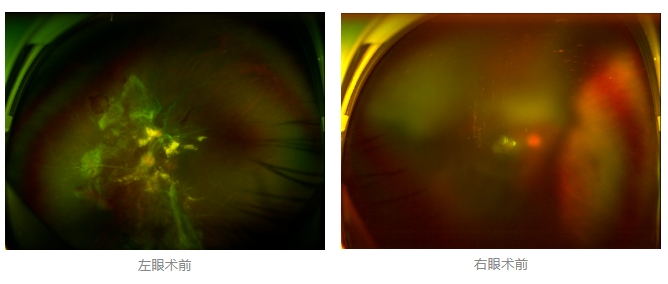

經(jīng)廈門眼科中心眼底病??菩姓魅瓮鯐圆z查后,確診其雙眼糖尿病視網(wǎng)膜病變VI期,伴發(fā)雙眼視網(wǎng)膜脫離和黃斑水腫,且右眼視網(wǎng)膜上增殖膜叢生,若再不盡快進(jìn)行治療,恐有失明風(fēng)險。

面對陳先生的復(fù)雜病情,王曉波主任采用玻璃體切割術(shù)聯(lián)合膜切除術(shù)等方式,精細(xì)剝離牽拉視網(wǎng)膜的增殖膜,復(fù)位脫離的視網(wǎng)膜,同時進(jìn)行玻璃體腔注藥促進(jìn)黃斑水腫吸收。

經(jīng)過規(guī)范化治療,術(shù)后2個月復(fù)查時陳先生的視力已有明顯改善,矯正視力從眼前指數(shù)提升至0.3,成功擺脫“失明危機(jī)”。但王曉波主任強(qiáng)調(diào):“這只是階段性勝利,后續(xù)治療不能松懈。”